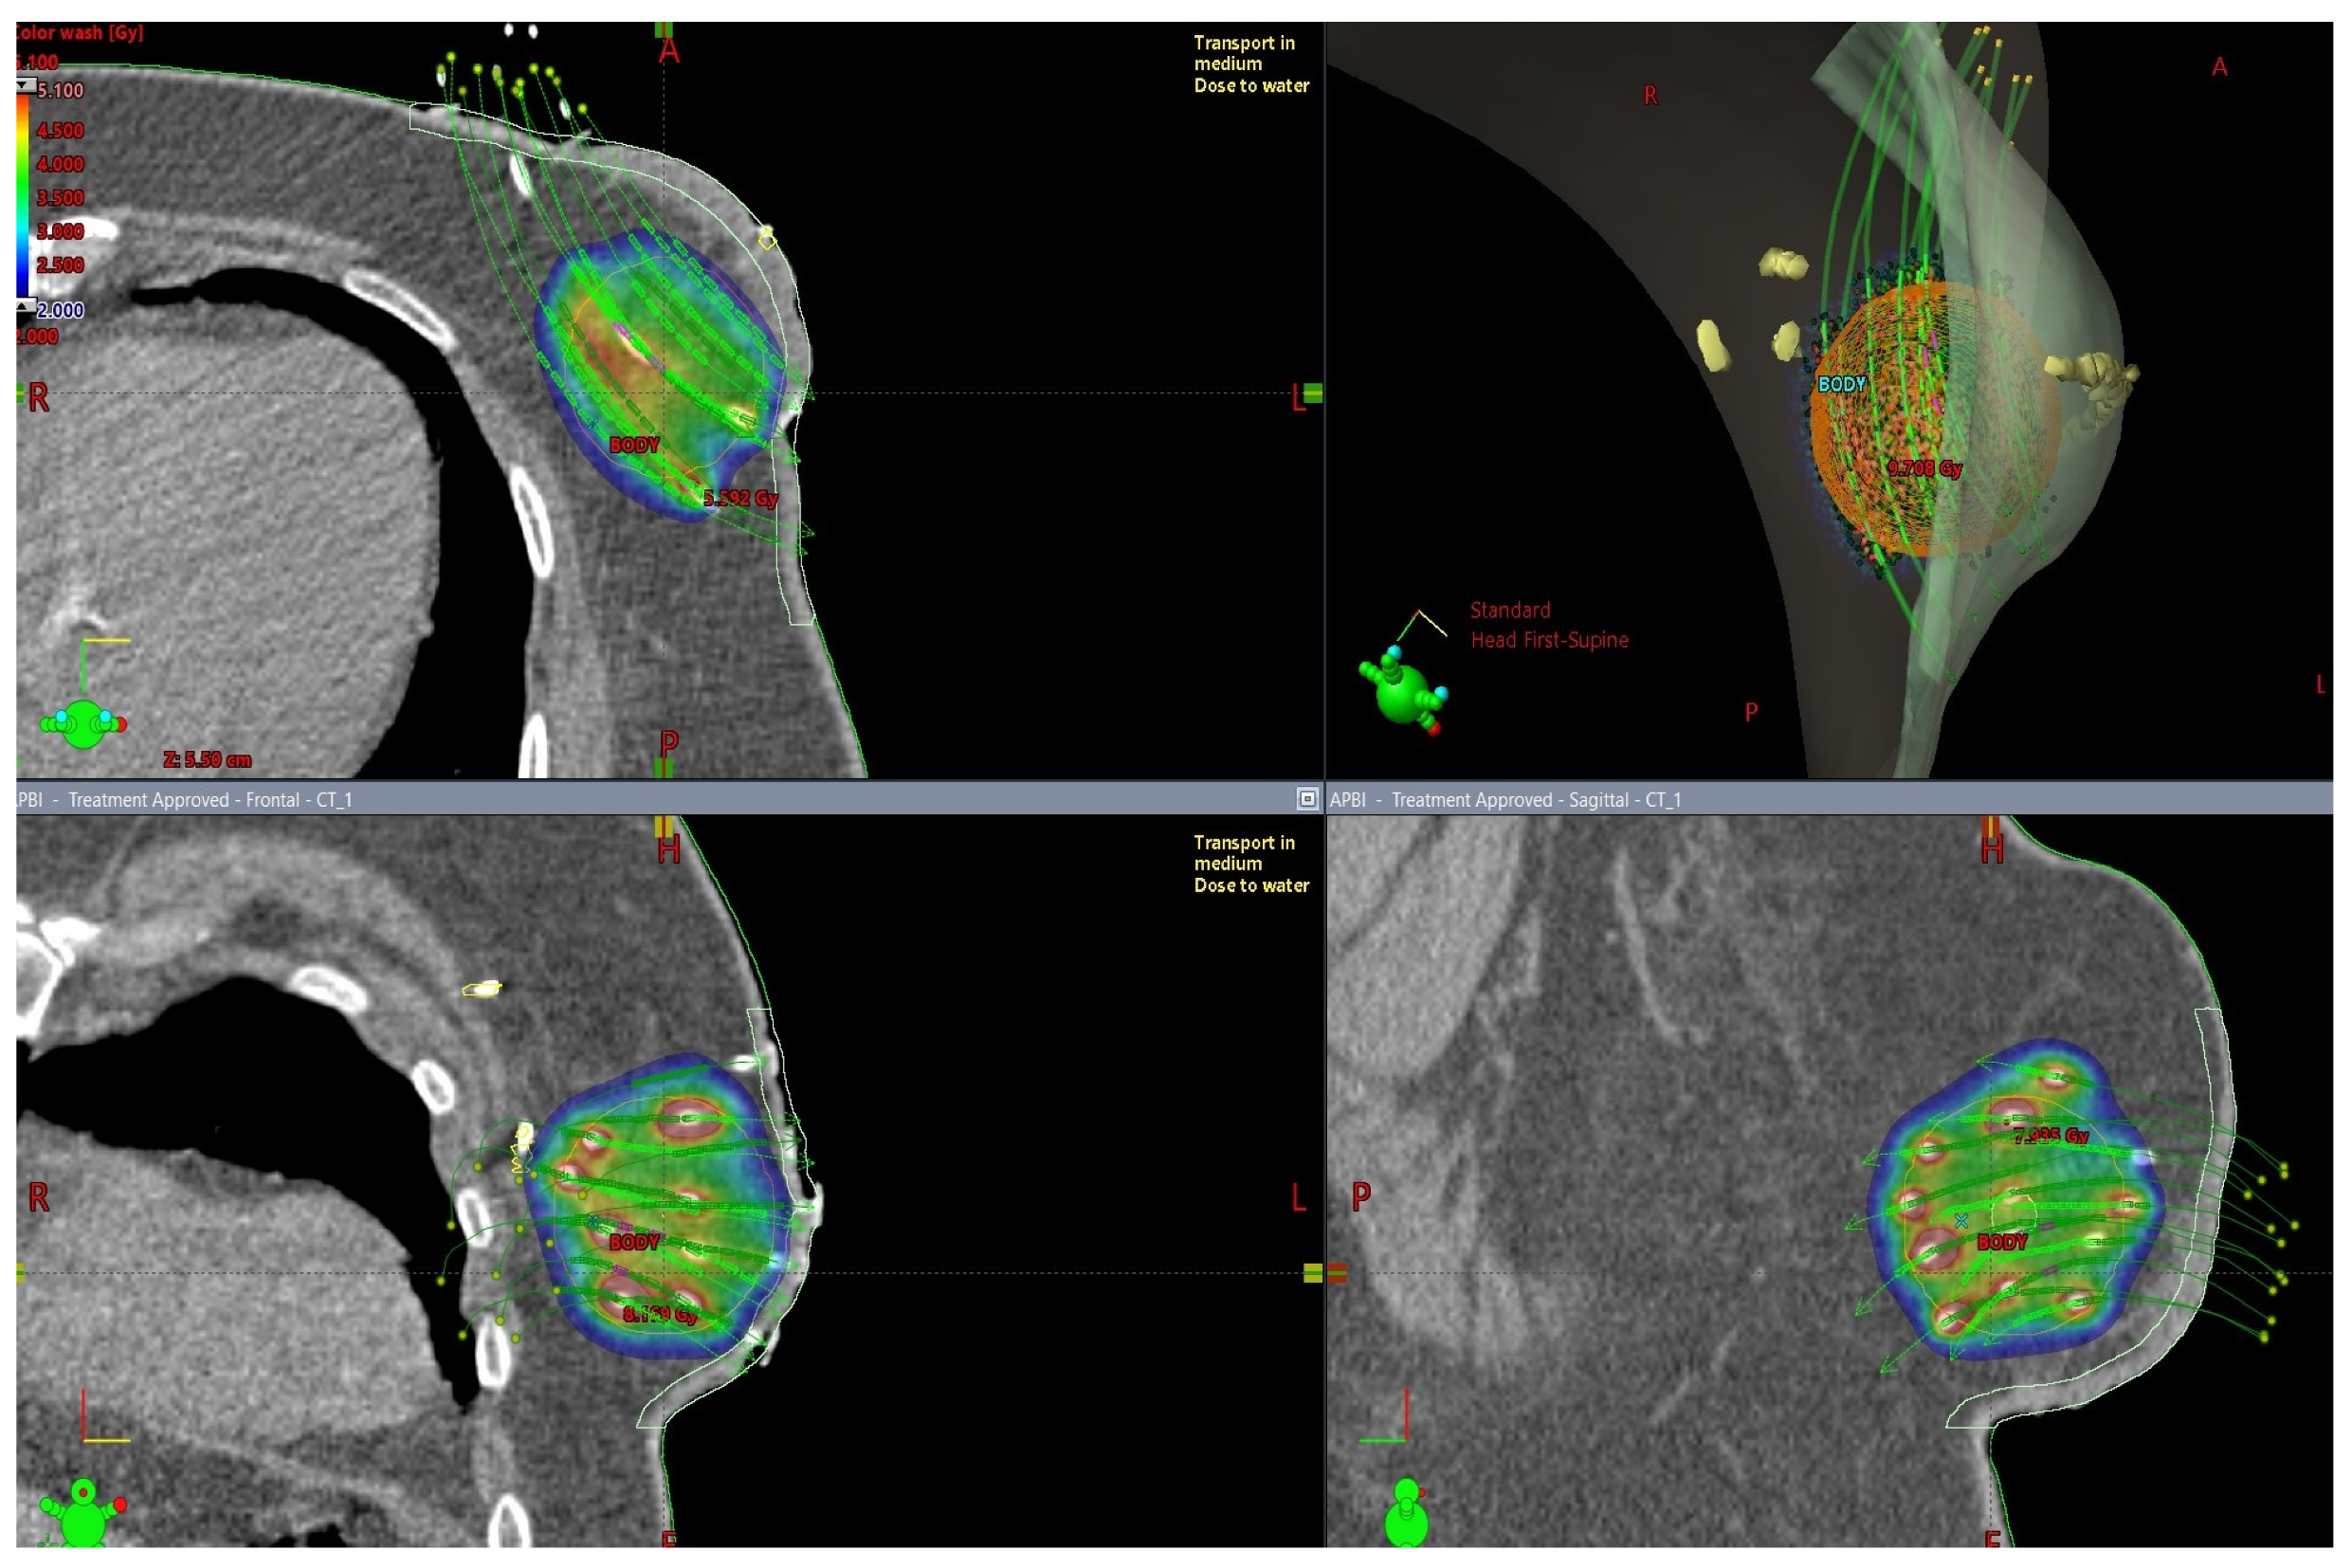

Radiation Biology for Medical Physicists - 1st Edition, Special Techniques of Adjuvant Breast Carcinoma Radiotherapy,

Special Techniques of Adjuvant Breast Carcinoma Radiotherapy, Breast Cancer - Radixact,

Breast Cancer - Radixact, Breast Cancer – Brachytherapy - Radiation Oncology | UCLA,

Breast Cancer – Brachytherapy - Radiation Oncology | UCLA,